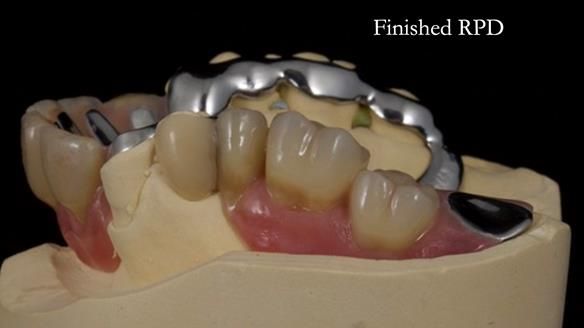

Keith’s case was one of the most challenging and rewarding cases I’ve treated this year. This 64 year old man presented with ill-fitting acrylic partial dentures that lacked stability, retention, and aesthetics. They constantly broke. He had lost the upper front teeth in a road traffic accident in his early 20s. The unopposed teeth had erupted, taking up space. After careful planning, we made a durable, metal-based upper partial denture/splint to address his dental concerns. He loved the outcome.

1. Denture design: A custom cobalt-chromium framework was Scandinavian-designed to maximise stability, protect the remaining teeth, and allow for future additions if needed.

Keith’s denture incorporated a Duracetal shell clasp on upper right first premolar (Myerson), which are designed to be virtually visible, providing a more aesthetic solution while enhancing patient comfort. The Scandinavian-inspired approach, based in modern removable prosthodontic techniques, ensured the denture was not only durable but also visually pleasing. Additionally, the design was carefully planned to allow for future modifications, ensuring that if Keith loses additional teeth, the denture can be adapted rather than replaced entirely.

I also used the Dahl concept to re-establish the occlusion upon fitting the RPD, which helped to intrude the lower left canine without needing to grind it too much.